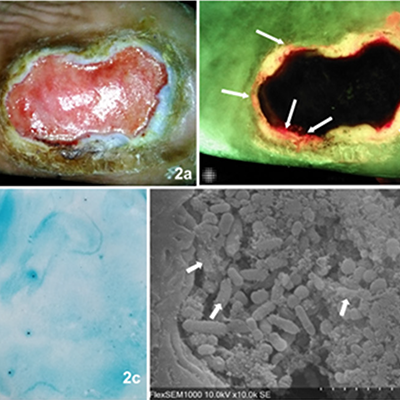

Detection of bacterial fluorescence from in vivo wound biofilms using a point-of-care fluorescence imaging device

Lopez, AJ et al. Int Wound J 2021

In vitro detection of porphyrin-producing wound bacteria with real-time fluorescence imaging

Jones, LM et al. Future Microbiol 2020

Assessing Biofilm at the Bedside: Exploring Reliable Accessible Biofilm Detection Methods

Mayer, P et al. Diagnostics 2024